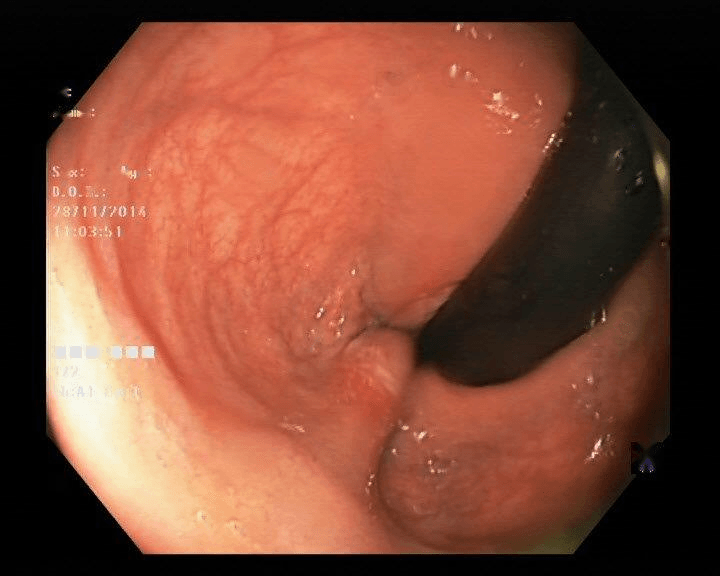

Refer to caption

(a) No abnormality

(b) Polyp

(c) Oesophagitis

(d) Ulcerative Colitis

Figure 1: Illustrations of question-answer pairs along with common abnormalities in gastrointestinal image from ImageCLEFmed-MEDVQA-GI-2023 dataset

The new dataset released for the ImageCLEFmed-MEDVQA-GI-2023 challenge is based on the HyperKvasir dataset [29], the largest gastrointestinal collections with more than 100,000 images, with the additional question-and-answer ground truth developed by medical collaborators. The development set and test set include a total of 3949 images from different procedures such as gastroscopy and colonoscopy, spanning the entire gastrointestinal tract, from mouth to anus. Each image has a total of 18 questions about abnormalities, surgical instruments, normal findings and other artefacts, with multiple answers possible for each, as shown in Table 1. Not all questions will be relevant to the provided image, and the VQA system should be able to handle cases where there is no correct answer. Figure 1 depicts several examples of question-answer pairs on common abnormalities in gastrointestinal tract, such as Colon Polyps, Oesophagitis, and Ulcerative Colitis. As shown in Figure 1(d), there are three possible answers to the question "What color is the abnormality?": "Pink," "Red," and "White", and a typical VQA system should be able to identify all three colors. In general, the image may contains a variety of noise and components that locates across abnormalities, such as highlight spots or instruments, which pose a significant challenge in developing efficient VQA systems for gastrointestinal domain.